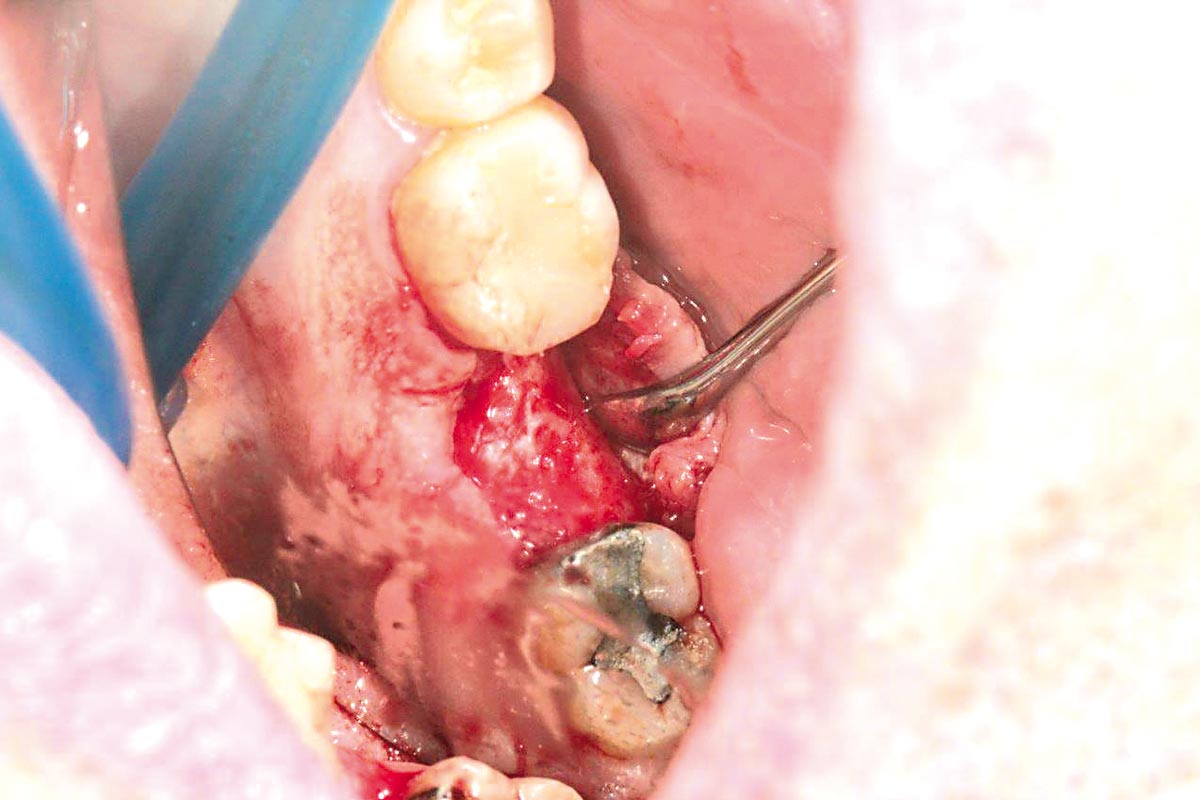

botiss cerabone® & Jason® membrane for horizontal augmentation - Clinical case by Dr. M. Steigmann

Three implants placed in a narrow posterior mandible